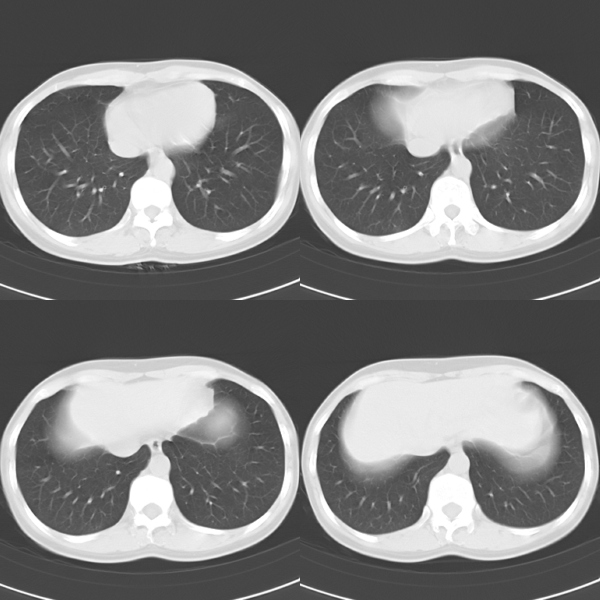

标题: CT19623:F40y,肋骨改变。

40岁女性,双侧胸部疼痛,以左侧为明显1+年。余无明显异常。

左侧肋骨单发膨胀性病变,皮质连续,病史较长,首先考虑良性病变:骨纤可能性大。